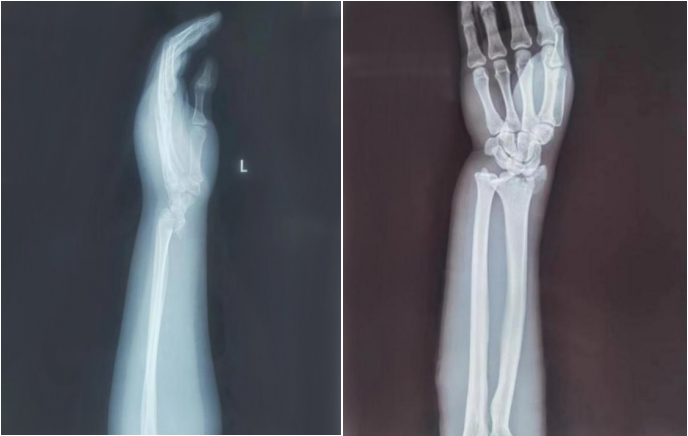

AED怎么自检手腕摔伤后自检方法及诊疗释疑_https://www.jmylbn.com_新闻资讯_第19张

常规/微创手术前

AED怎么自检手腕摔伤后自检方法及诊疗释疑_https://www.jmylbn.com_新闻资讯_第20张

常规/微创手术后